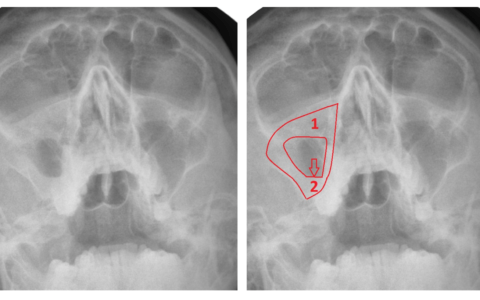

КТ-снимки хронического этмоидита: подробная визуализация

Раздел: Фотодневник открытий